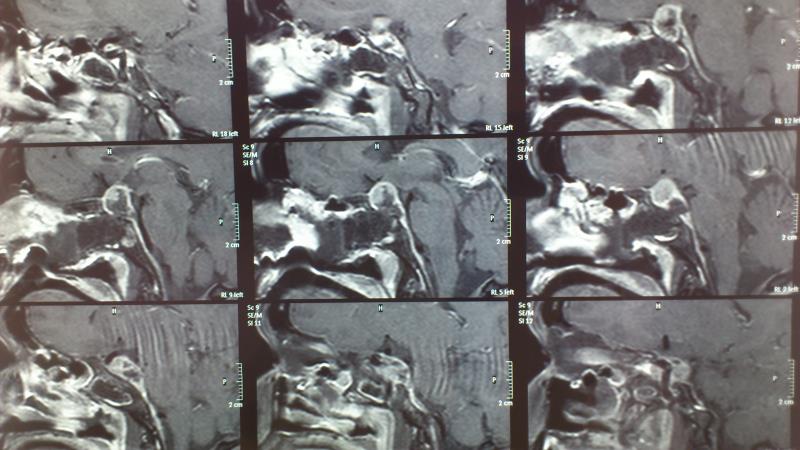

Προεγχειρητικός απεικονιστικός έλεγχος